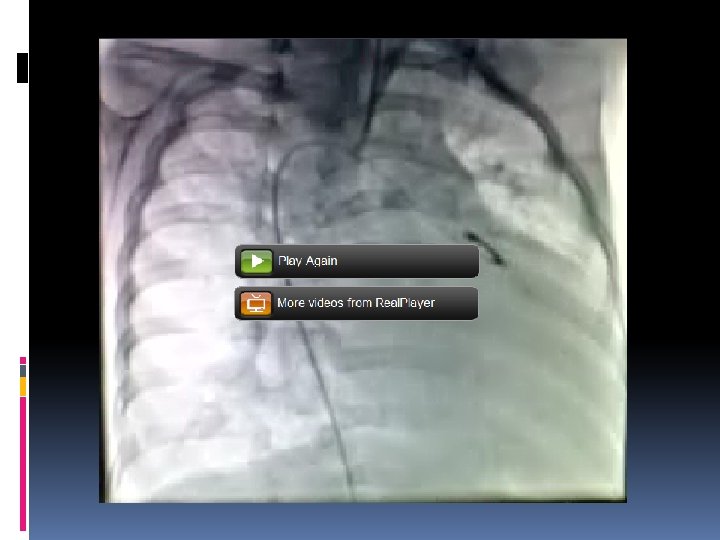

Findings and procedure Truncus type I, right sided aortic arch RPA & LPA 10 mm Tricuspid truncal valve with regurgitation due to redundancy of posterior truncal cusp Rastelli operation (using 13 mm pulmonary homograft)